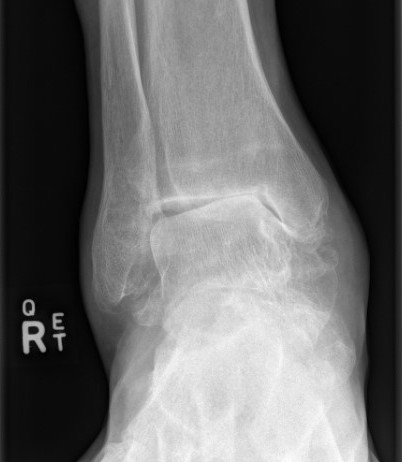

Leslie et al Foot Ankle Int 2023

- systematic review of CT confirmed union rate after ankle fusion in 237 ankles

- union rate 86%